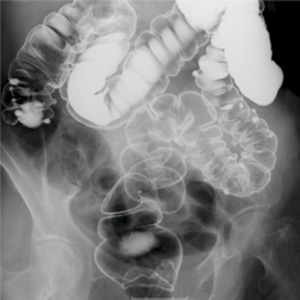

- 消化管造影検査(食道・胃・小腸・大腸検査) 造影剤(バリウム)を使って消化管を観察する検査です。

Q2) どうして胃や大腸の検査の時、回転したり体を動かしたりするのですか?

|

![]() |

A2) 胃や腸の壁の内側にバリウムを付着させて観察する検査なのでムラなく壁全体にバリウムを着けるためです。 |